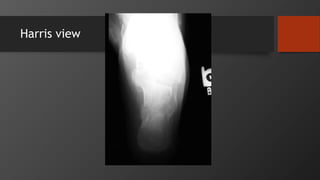

Imaging

• AP, Lateral

• Harris view

• CT scan

• Gold standard

Harris view